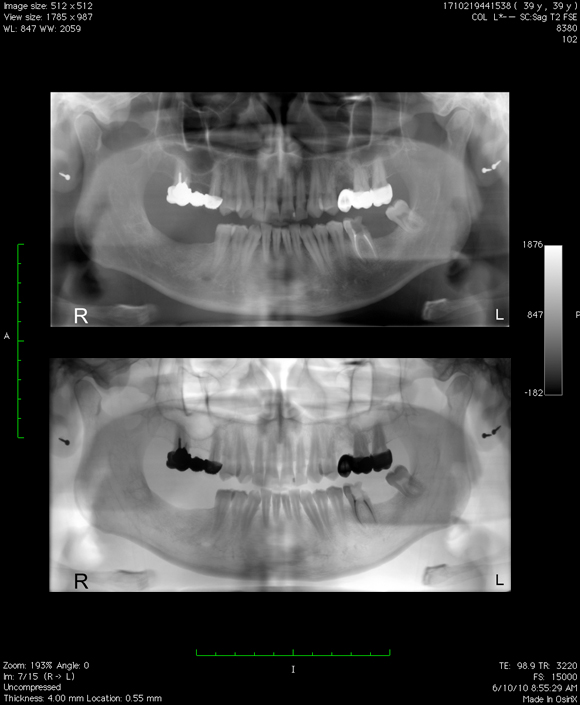

Ma tot gandesc de ceva timp la o noua schimbare pentru fotografiile de la biografie si m-am decis, intr-un fel anume, diferit de imaginile clasice, RADIOGRAFII . Radiografia este ruda cu fotografia, dex-ul spune ca ea reprezinta fotografierea interiorului unui corp opac, in special a unor regiuni din interiorul corpului omenesc sau animal, cu ajutorul razelor x, practic, conform dex-ului, va prezint mai mult… A patra din pacate nu a iesit cum imi inchipuiam aparatul de fotografiat fiind oarecum estompat din cauza unghiului prost ales, din pacate nu am putut s-o refac deoarece 3 radiografii/zi inseamna o cantitate suficient de mare de radiatii.

p.s. Am completat cu o panoramica dentara, cu un RMN la coloana si cu doua radiografii cervicale. Seria continua !